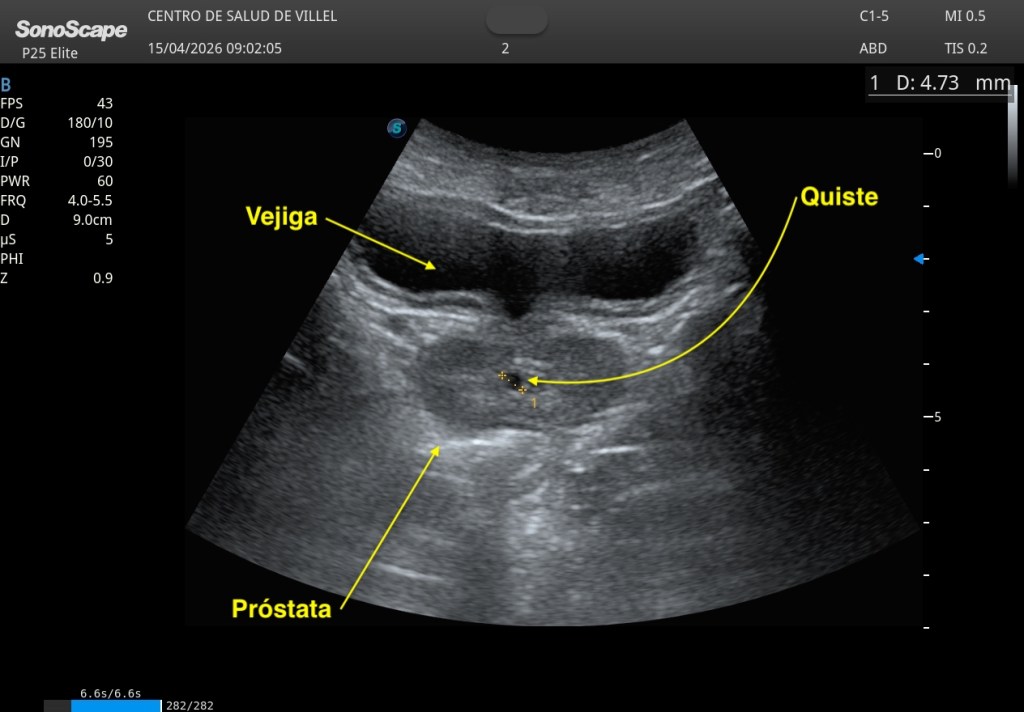

En un paciente joven, de unos 20 años, se identificó una pequeña imagen anecoica, central, localizada en la próstata, de aproximadamente 5 a 10 milímetros en su eje longitudinal mayor, bien delimitada, de apariencia quística y sin signos ecográficos de complejidad. Una imagen pequeña, sutil incluso, pero con una localización muy característica. Aquí te dejo las imágenes clave:

Ante una lesión quística medial prostática en un paciente de esta edad, inevitablemente surge la sospecha y hay que consultar con el radiólogo responsable. Se documenta muy bien, y se comenta con el radiólogo, como he mencionado previamente.